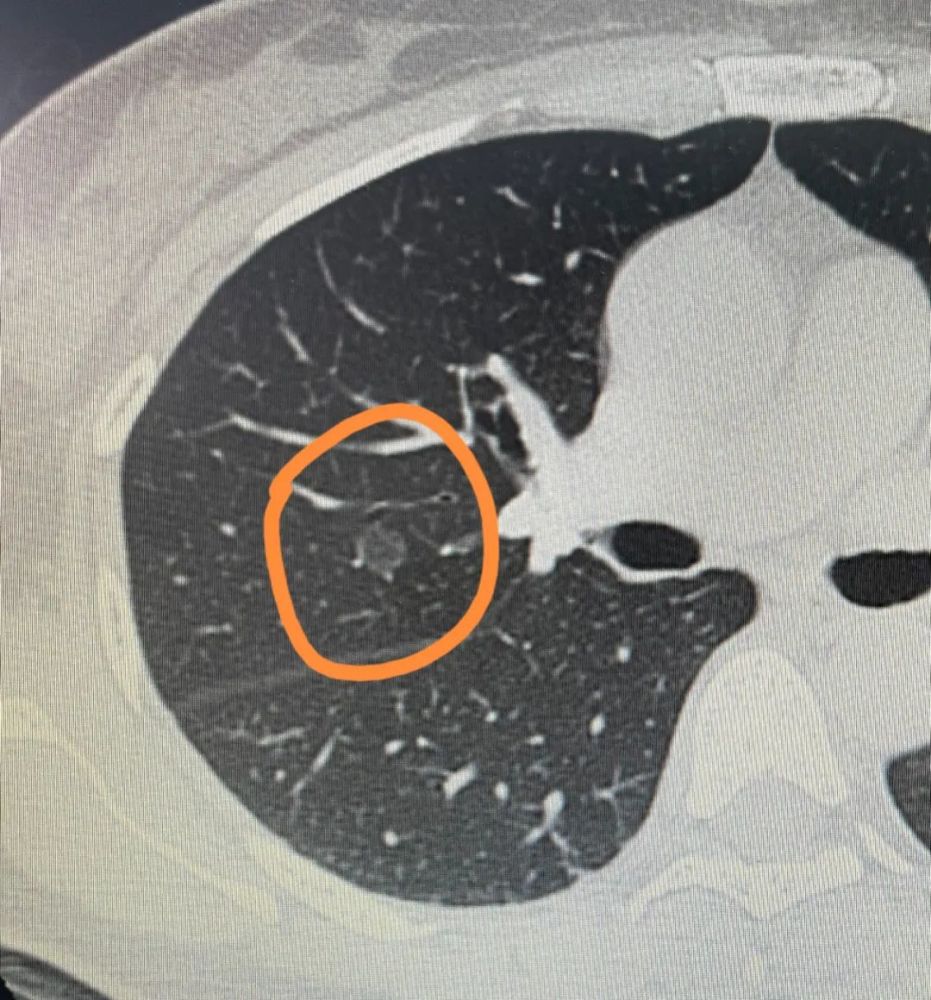

肺结节 钙化灶

肺结节 钙化灶,肺结节钙化灶

肺结节钙化灶

肺钙化灶

肺钙化灶图片

肺钙化灶是什么意思

肺钙化

肺部结节

肺结节良性

肺结节片子

肺磨玻璃结节